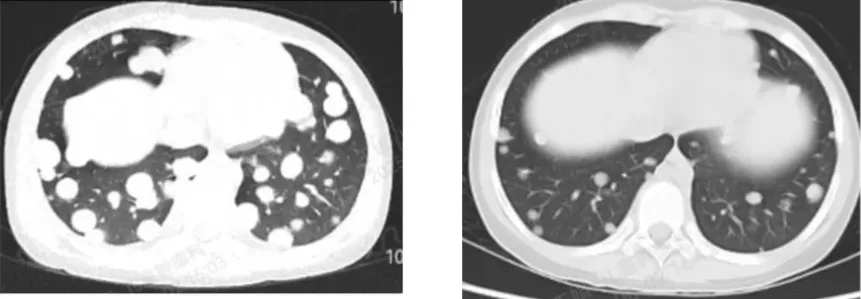

1代NTRK抑制剂耐药,ICP-723治疗后肿瘤显著缩小

一位软组织恶性梭形细胞肿瘤伴肺部转移的患者,基因检测显示ETV6-NTRK3融合,接受化疗和9个周期的第一代TRK抑制剂后出现疾病进展。在国内接受5个周期ICP-723的治疗后,肺部非靶病灶明显缩小、右大腿靶病灶达到手术条件,右大腿病灶手术切除后病理提示已未见肿瘤组织。